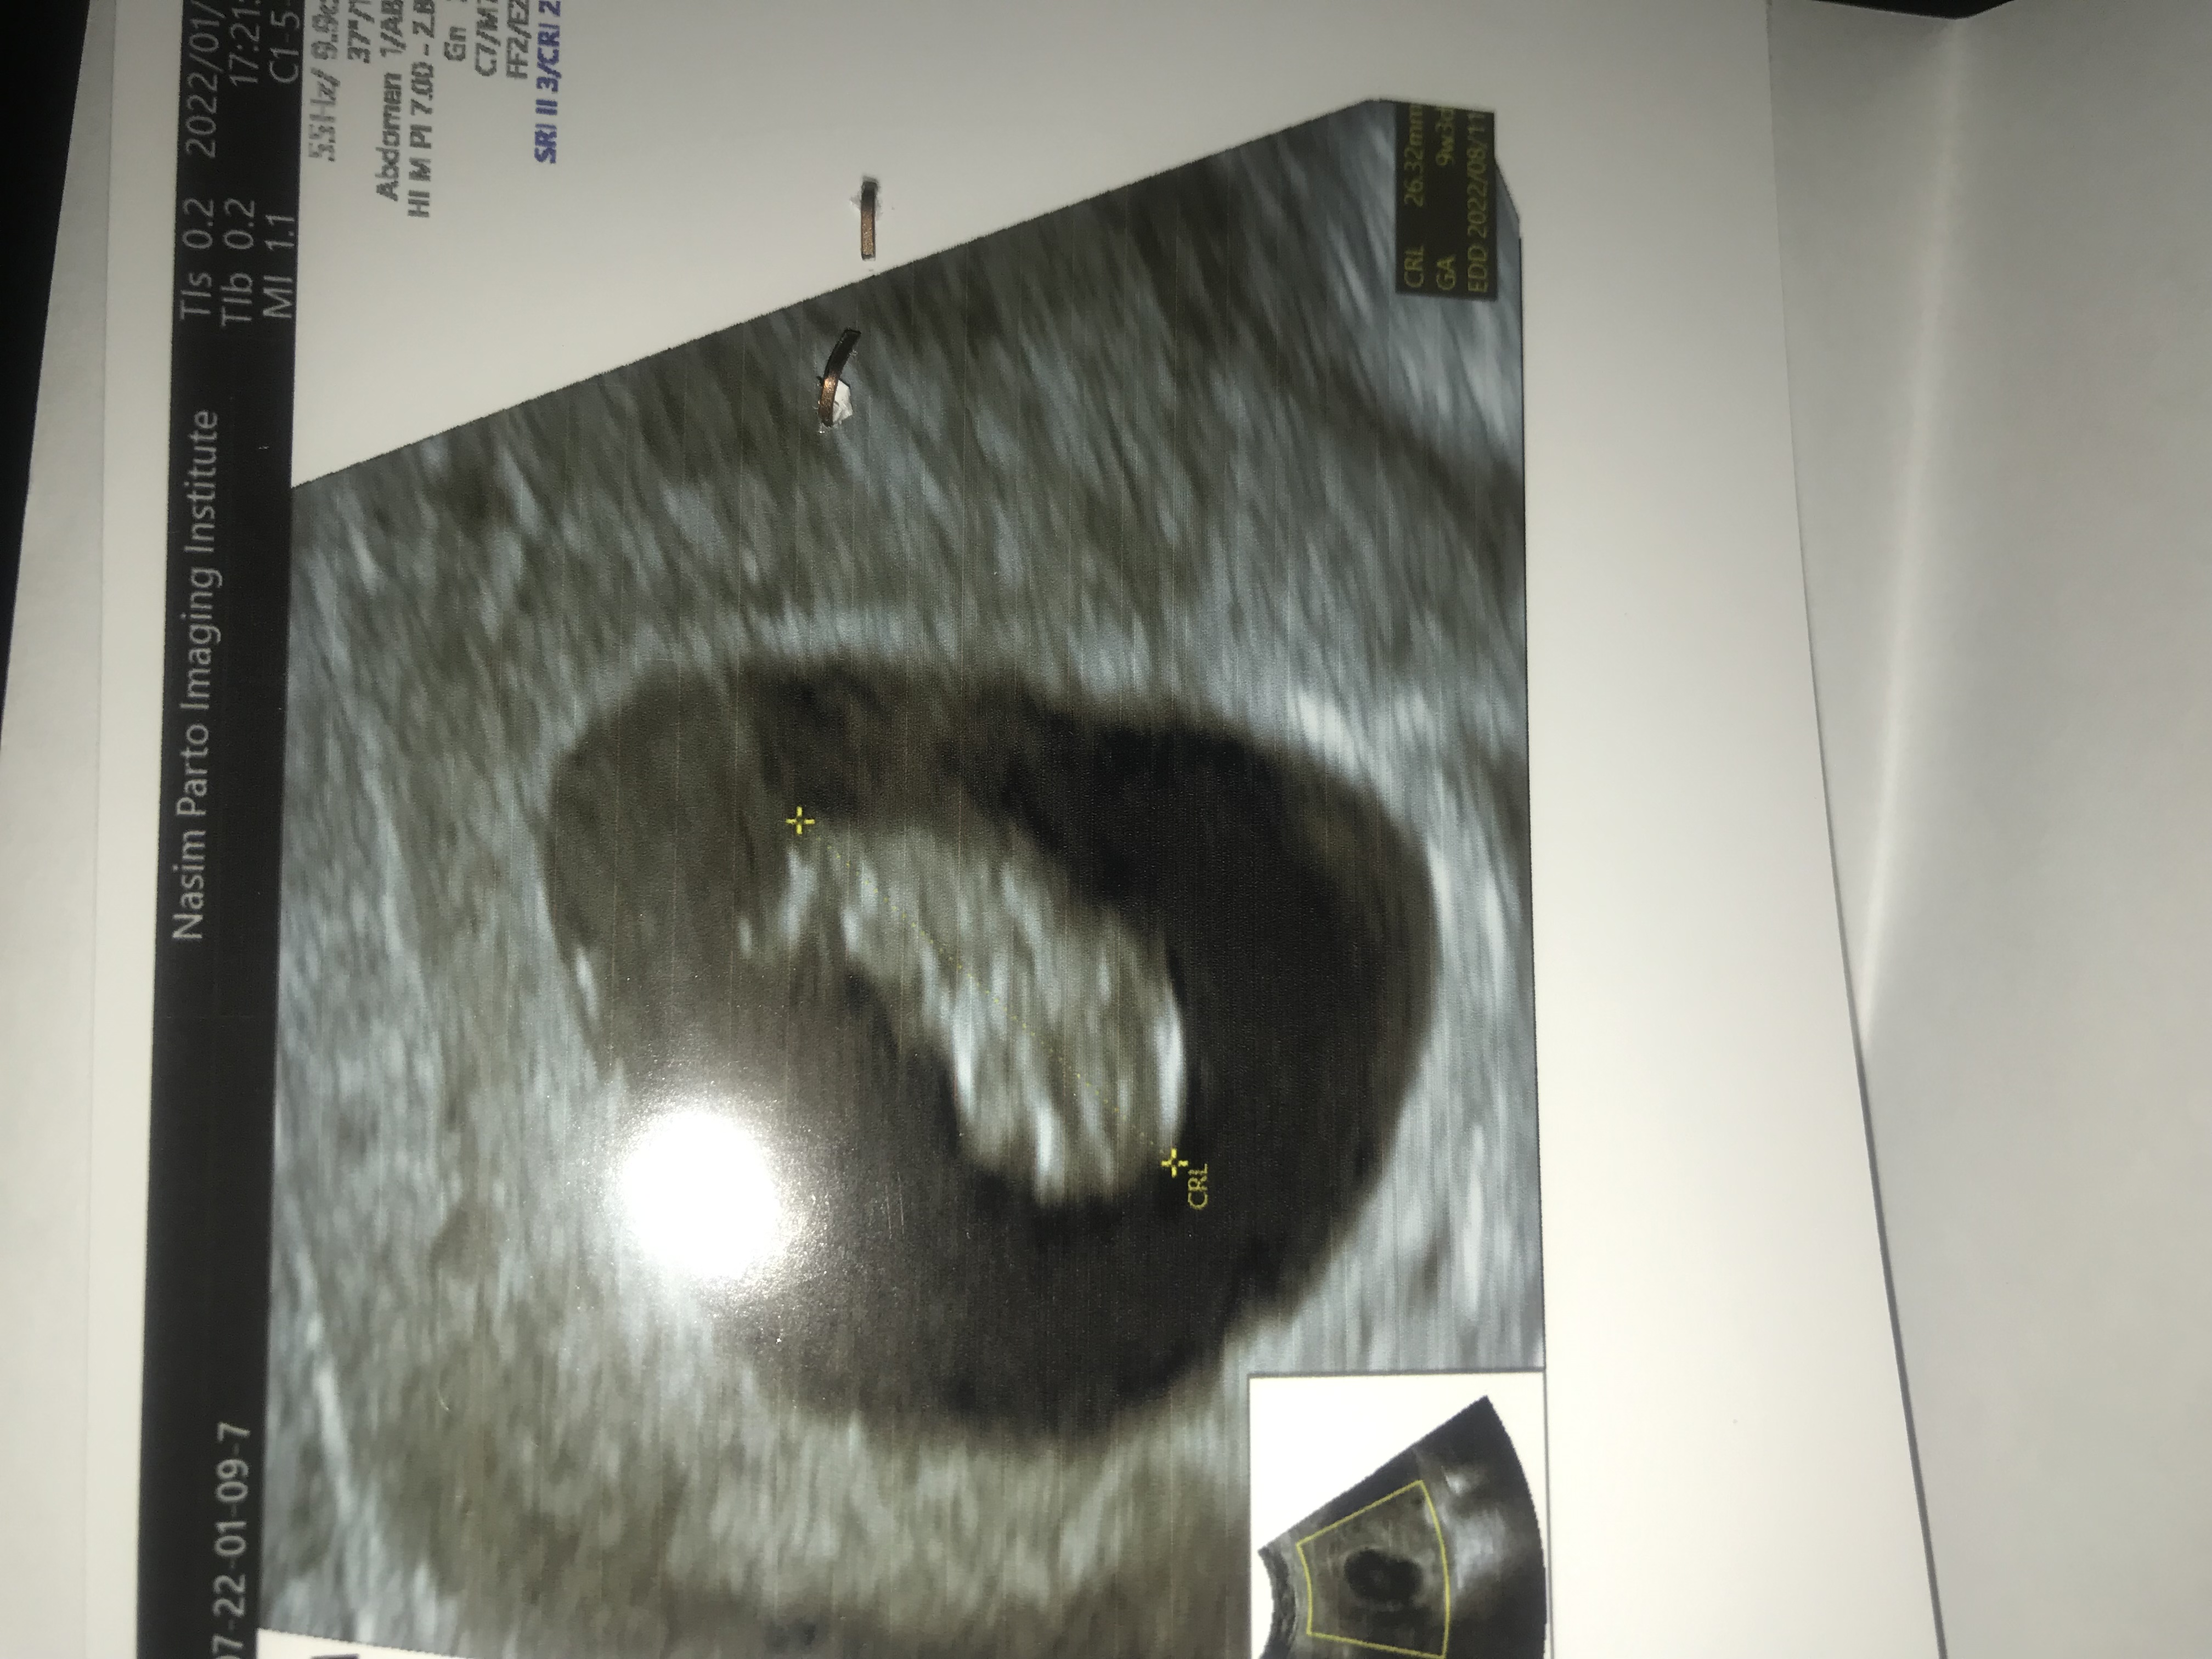

عکس سونوی۸ هفته رو نگا کن

اگه توی عکس نی نی سمت چپ باشه میشه راست شکمت پس میشه پسر و برعکس

حالا به شرطی که سونو شکمی باشه

عکس سونوی۸ هفته رو نگا کن اگه توی عکس نی نی سمت چپ باشه میشه راست شکمت پس میشه پسر و برعکس حالا به ...

من نه هفته و سه‌روز بودم رفتم سونو بعد وسطه 🤣🤣🤣چجوری تشخیص بدم؟

واقعا دقیقا وسطه تاحالا اینقدر وسط ندیده بودم😂

البته فکر کنم چون نه هفته بودی جاش مشخص نیست اکثرا سونو قلب ۶ هفته میرن کناره جا میگیره بچه